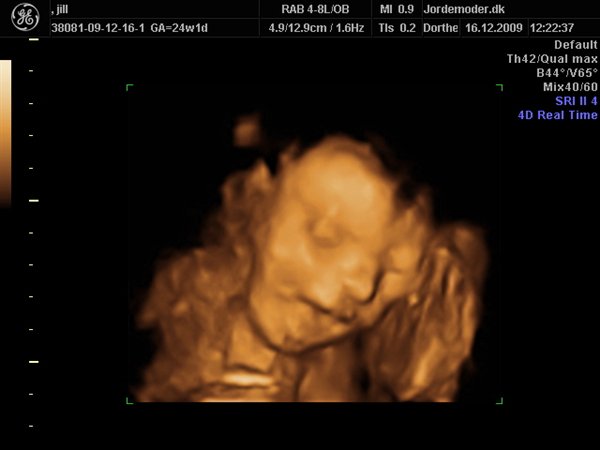

Da jeg snakkede med hende i dag sagde hun at fra uge 27 til og med uge 31 var det bedste tidspunkt at få det gjort....

Vi skal give 1400 kr for 45 minutters total gennem scanning, hvor hun fortæller, undersøger babyen fra top til tå, laver vægtskøn også får vi billeder og dvd med hjem.... Og ja det er da mange penge, men min forlovede har haft en masse vikar timer den her mdr, også sagde han at han syntes vi skulle bruge de penge på noget vi normalt ikke ville have gjort. Han sagde egentlig at jeg kunne gå ud og shoppe for dem, men jeg har termin om ti uger, så gider ærlig talt ikke bruge penge på nyt graviditets tøj, så hellere det her som vi egentlig havde valgt fra pga prisen, men som vi begge to rigtig gerne vil....